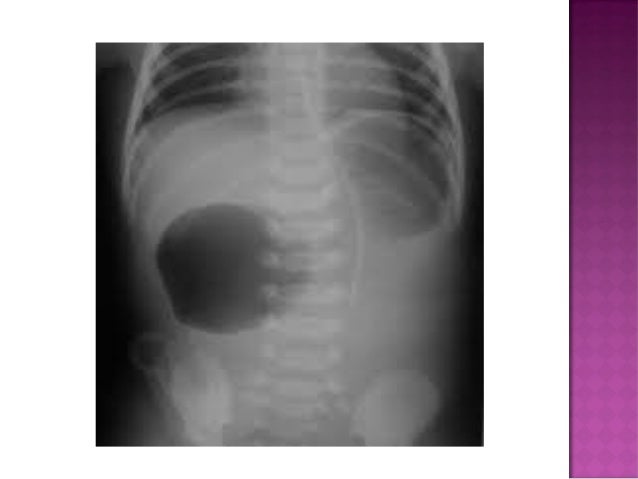

Small left colon sydrome is subset of meconium plug syndrome in which an enema demonstrates an apparent transition zone between the dilated and the normal-to. Plain abdominal radiographs show dilated intestinal loops. Affected patients have abdominal distention difficulty in initiating evacuation and sometimes vomiting.

Neonatal small left colon syndrome is rare but an important differential in this situation and radiological findings are diagnostic. Neonatal small left colon syndrome is rare but an important differential in this situation and radiological findings are diagnostic. Its etiology remains unknown but a significant association has been noted between maternal diabetes and small left colon. Meconium plug syndrome small left colon syndrome long segment Hirschsprung disease The rectosigmoid ratio was greater than 1 favoring meconium plug syndrome. Infants with small left colon syndrome present with progressive abdominal distention vomiting and failure to pass meconium. MATERIAL AND METHOD Nineteen infants presented inthe first to third days oflife each ofwhom had essen-tially the same clinical history suggesting low colonic obstruction. Plain abdominal radiographs show dilated intestinal loops.